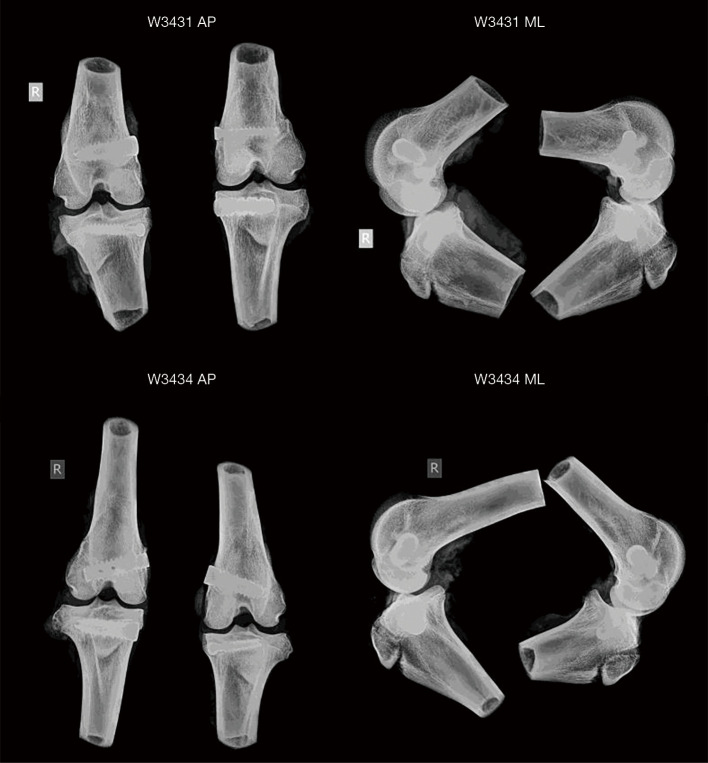

Methods: We evaluated the in vivo performance of three titanium alloy implants: (A) iFuse-TORQ implant; (B) Fenestrated Sacroiliac Device; and (C) Standard Cancellous Bone Screw in the cancellous bone of the distal femur and proximal tibia in 8 sheep. Group A was produced using additive manufacturing [three-dimensional (3D) printing] while Groups B and C were made with traditional methods. The vivo responses of the implants at the implant-bone interface were examined using mechanical testing (push out and removal torque), polymethyl methacrylate (PMMA) histology combined with fluorochrome labels and quantitative histomorphometry of bone ongrowth, ingrowth and through growth at 3 and 6 weeks.